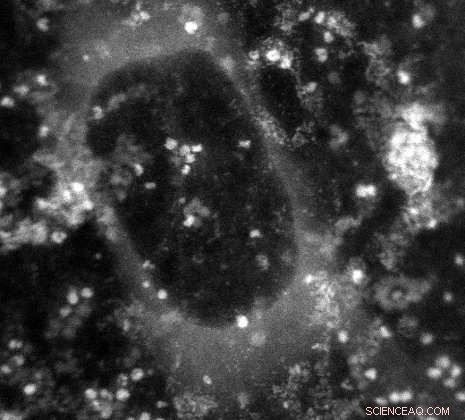

In this image generated by an electron microscope, the white dots are the protein ferritin. The dark circle in the middle is a bubble of water vapor trapped within the graphene capsule enclosing the sample.

The team tried their technique on a biochemical that plays a major role in human health: ferritin. "It's a protein that stores and releases iron, which is critical for many body functions, and if ferritin isn't working right, it may be contributing to lots of diseases, including Alzheimer's and cancer," Shokuhfar said.

The team made a microscopic sandwich, with ferritin immersed in water as the filling and graphene as the bread, and sealed the edges. Then, using a scanning transmission electron microscope, they captured a variety of images showing ferritin's atomic structure.  In addition, they used a special type of spectroscopy to identify various atomic and electronic structures within the ferritin. Those images showed that the ferritin was releasing iron and pinpointed its specific form.